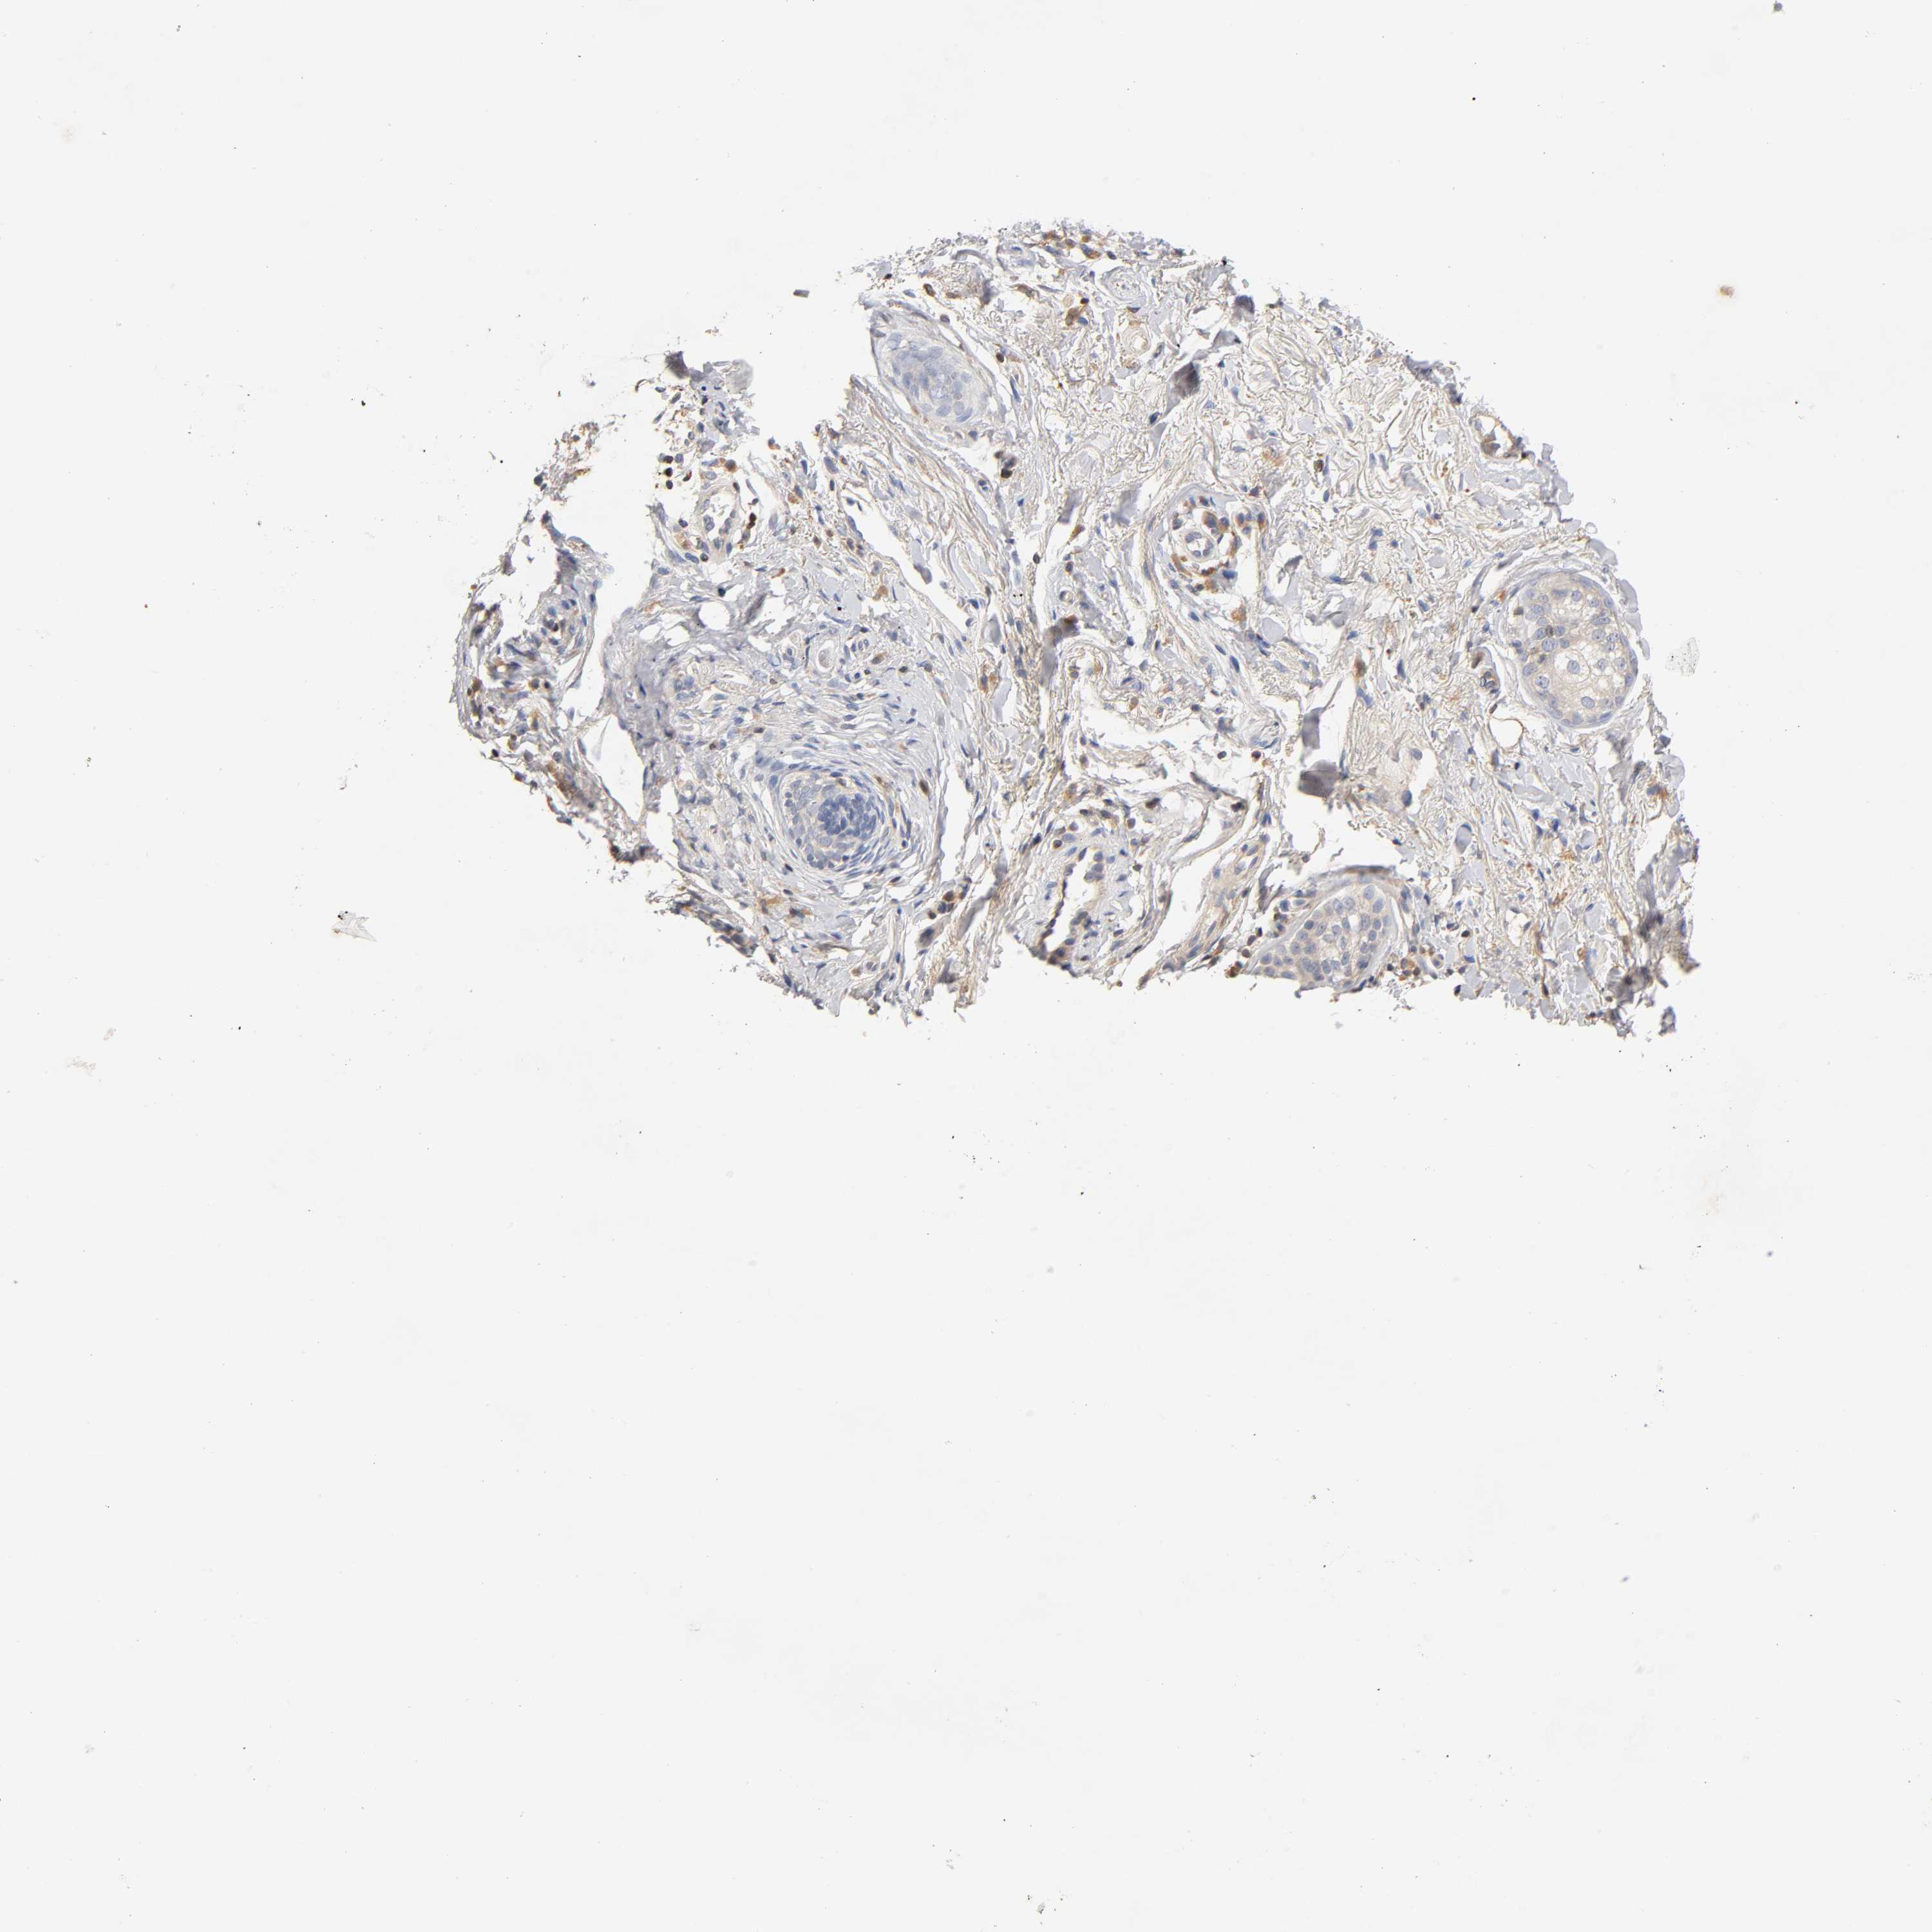

SKIN CANCER - Protein expressioni

A mouse-over function shows sample information and annotation data. Click on an image to view it in a full screen mode. Samples can be filtered based on level of antibody staining by selecting one or several of the following categories: high, medium, low and not detected. The assay and annotation is described here.

Antibody stainingi

Antibody staining in the annotated cell types in the current human tissue is reported as not detected, low, medium, or high, based on conventional immunohistochemistry profiling in selected tissues. This score is based on the combination of the staining intensity and fraction of stained cells.

Each image is clickable and will lead to virtual microscopy that enables deeper exploration of all samples and also displays staining intensity scores, fraction scores and subcellular localization as well as patient and tissue information for each sample.

Antibody CAB005052

Squamous cell carcinoma, NOS

Basal cell carcinoma